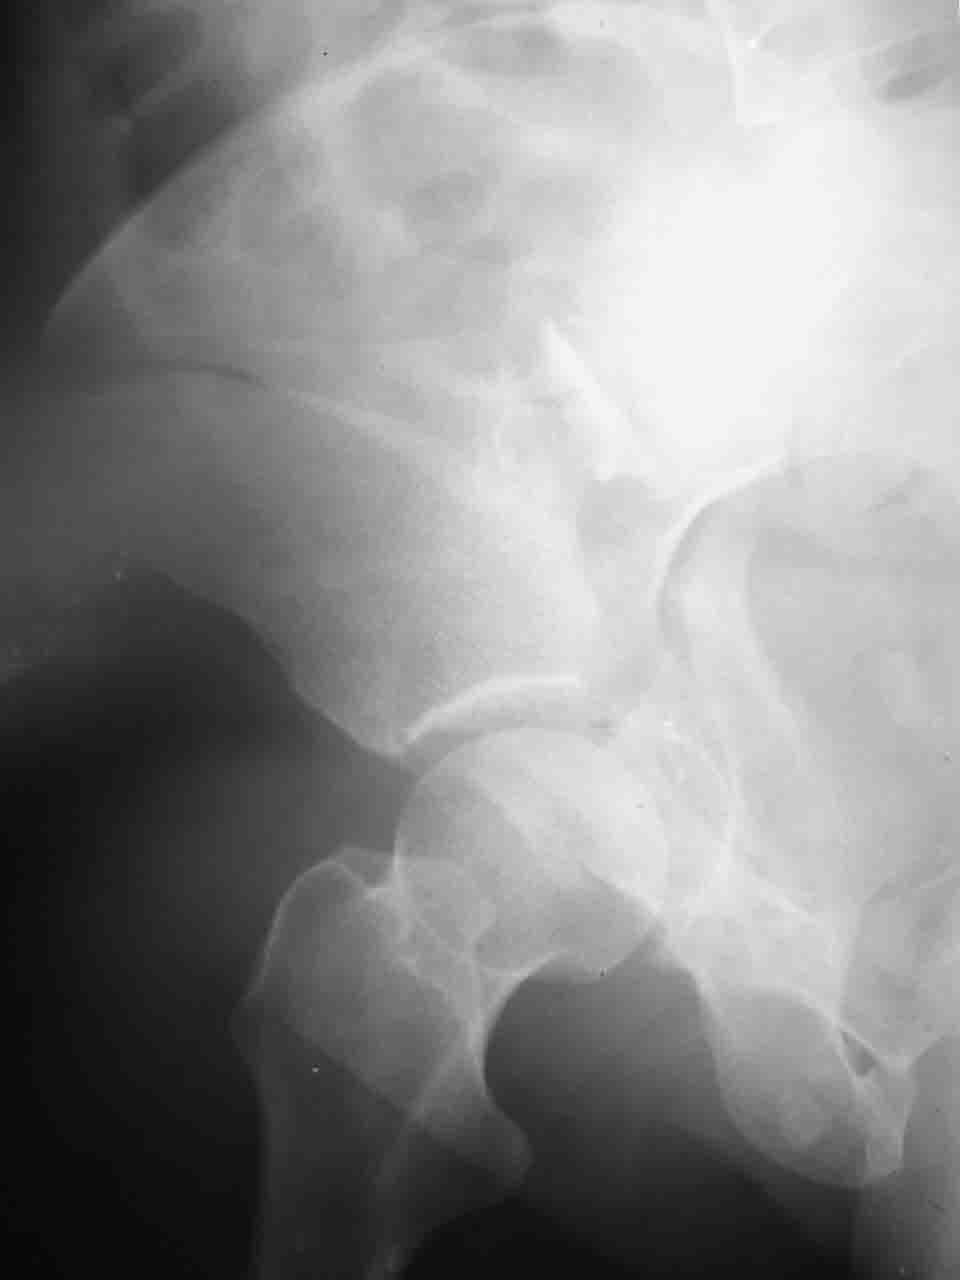

А какой отдел вертлужной впадины более важен передний или задний? Чем был обусловлен выбор доступа к суставу? Проще говоря, почему вы пошли передним доступом на двухколонный перелом? Мне понятны ваши сомнения, когда не удется сделать все что хотелось бы. В данном случае доступ должен быть чрезвертельным боковым (как и советовал Рунков) или двумя доступами.

Логика подсказывает, что все-таки лучше иметь анатомически полноценную впадину, хотя ранее упоминалось состояние вторичной конгруэнтности и одно наблюдение у меня есть, когда у больного с полностью нарушенной анатомией впадины и подвывихом головки бедра кзади и кверху боли отсутствовали при относительно достаточном для стиля жизни больного объёме движений. Но это только одно наблюдение и кроме перелома впадины у этогобольного была и тяжелая ЧМТ в анамнезе. Основываясь на формулировке структуры ацетабулюм Э. Летурнеля - как перевернутой буквы Y, впадина для полноценной функции сустава должна иметь сферичность, соответствующую размеру головки бедра и если один из компонентов в дефиците, то функциональные последствия рано или поздно проявятся.

> передним доступом на двухколонный перелом?

Илеофеморальный доступ не совсем передний и сравнительно с илеоингвинальным, и Кохера-Лангенбека открывает весь наружный таз кроме самых передних отделов лонных костей, фиксацию которых я не ставил в задачу. Обширность диссекции, большая длительность операции и более высокий риск гетерооссификации - отрицательные моменты в обмен на возможность легче ориентироваться.

Вопрос доступа к вертлужной впадине при остеосинтезе задача не простая. Конечно, у Летурнеля и Тайла всё давно описано, нам остается только брать на вооружение. Но сами понимаете, что не бывает двух одинаковых ситуаций, поэтому в каждом случае вопрос решается сугубо индивидуально. Наша главная цель - восстановить анатомию с нанесением минимальной дополнительной травмы тазобедреннному суставу, думаю с этим никто не поспорит. Расширенный илиофеморальный доступ уж слишком травматичен (как сказал один коллега "таз лежит отдельно, больной отдельно").Стоит ли делать из пациента анатомический препарат для того чтобы легче ориентироваться. Да и нужно ли собирать всю "мозаику"? Мы применяли при таких операциях своеобразную операционную хитрость - сначала устраняли грубое смещение крыла под гребнем с фиксацией так называемой "плавающей" пластиной (временно фиксированной на двух винтах)- доступ или продлевали боковой, или делали небольшой дополнительный разрез над гребнем. Это позволяло устранить грубое смещение и захождение отломков тела повздошной кости, что значительно облегчало репозицию и остеосинтез впадины над сводом. Основное внимание конечно же уделяли нагружаемому задне-верхнему отделу. Сообщите ваш адрес, пришлю схемы и рентгенограммы.